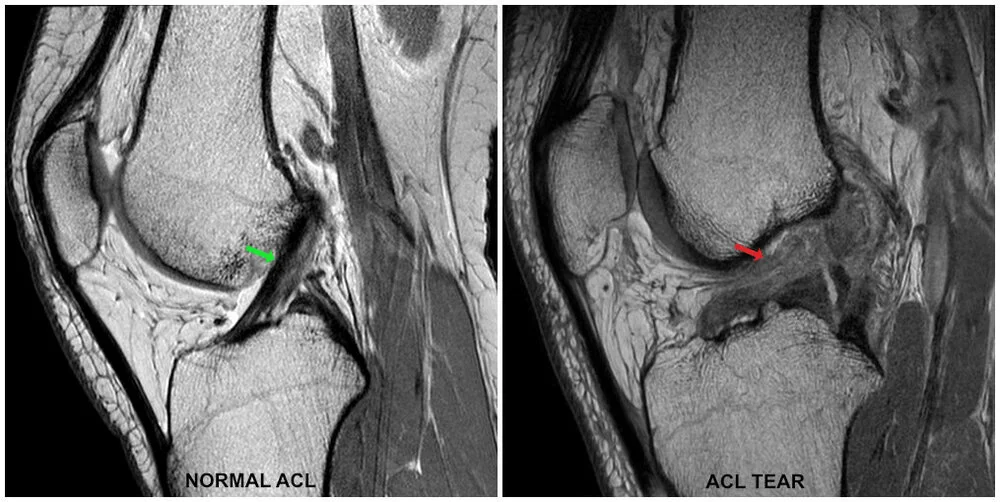

ACL (Anterior Cruciate Ligament) reconstruction is a surgical procedure used to replace a torn ACL in the knee. The ACL is a crucial ligament that helps stabilize the knee joint. When it gets injured, it can cause pain, instability, and difficulty in movement. This surgery is commonly performed on athletes and active individuals who need to restore knee function for daily activities and sports.